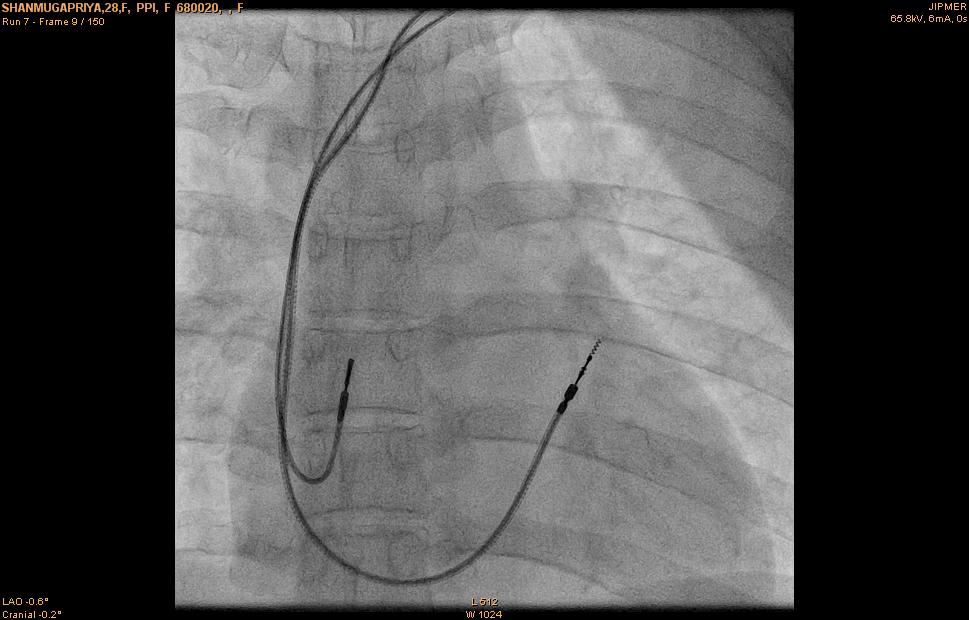

VDD lead

VDD lead placement

• Similar to RVA lead

• Inter-electrode distance

• Position the bipole